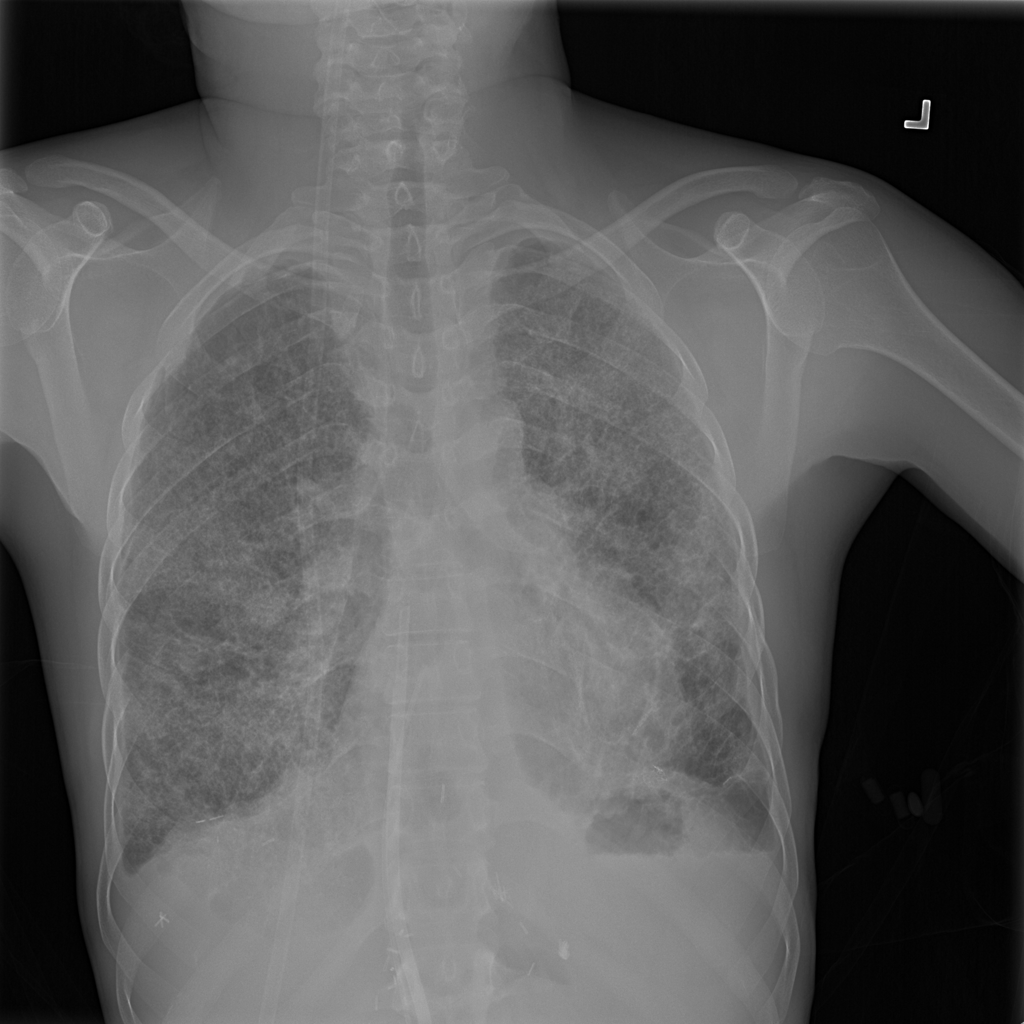

PAT-4639 · IMG-011Pneumothorax

PAT-4639 · IMG-011

AP